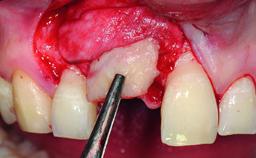

A 49-year-old female patient was referred for implant therapy to replace the upper right central incisor (tooth 11). The tooth had been assessed by an endodontist who diagnosed a vertical fracture of the root. The tooth had a hopeless prognosis and needed to be extracted. The patient was healthy and was not taking any medications. She was allergic to penicillin. The patient had high esthetic demands but her expectations were realistic. The extraoral examination revealed no facial asymmetries. The right temporomandibular joint demonstrated an opening click but was otherwise asymptomatic. The lip line was high with a significant gingival display.

| Bone Augmentation | Simultaneous|Vertical |

| Augmentation Materials | Autogenous chips|Xenogenous|Membrane |